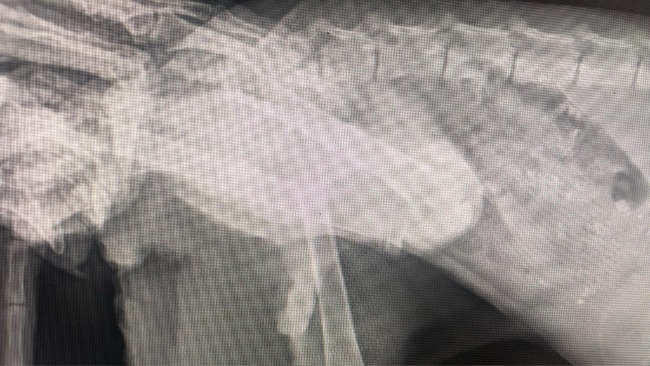

Edit: ZŁAMANIE Z PRZEMIESZCZENIEM!!!

Kociakowi ZWISA tylna łapa!!! Ten kociak ledwo chodzi! Prawdopodobnie potrzebna amputacja, ale to stwierdzi lekarz. Kot do nas właśnie jedzie. Już teraz wiemy, że potrzebne są nam fundusze na diagnostykę: